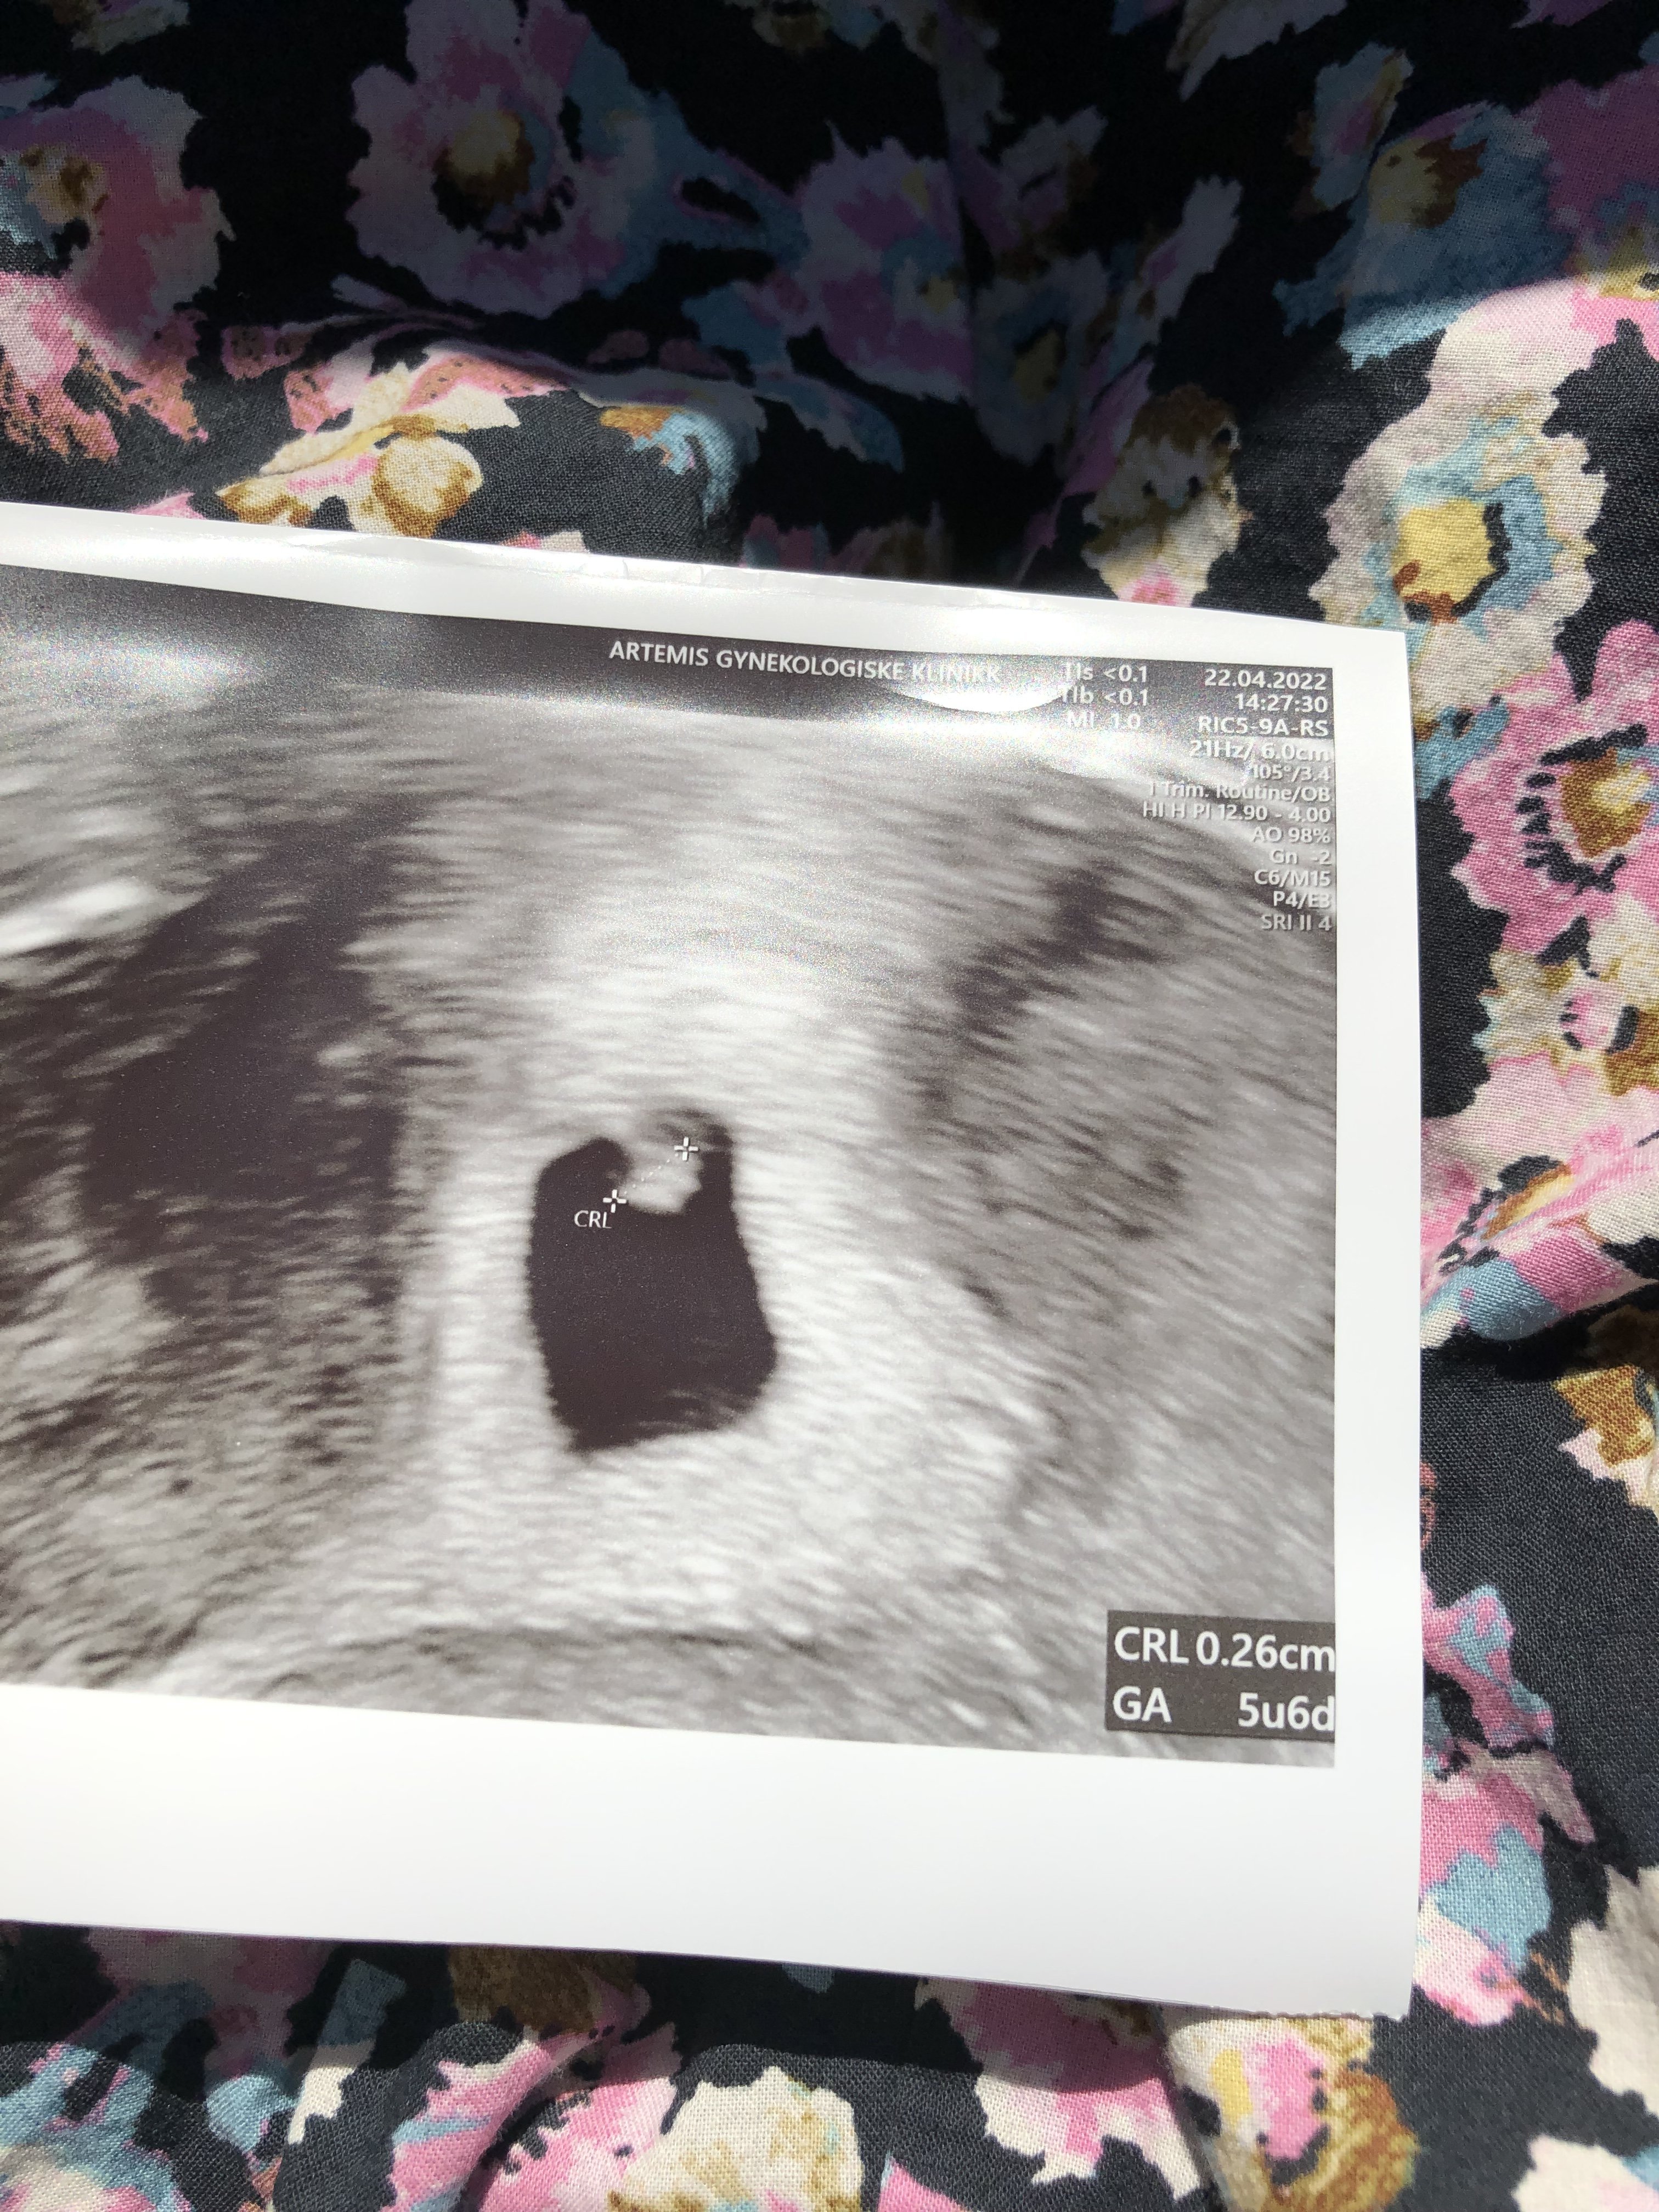

Verdi på 9500, doblingstiden ser flott ut. Spottingen er fremdeles borte og kvalmen er kommet i bølger.

Neste steg tidlig UL på fredag

Vis vedlegget 380563

Vis vedlegget 380564